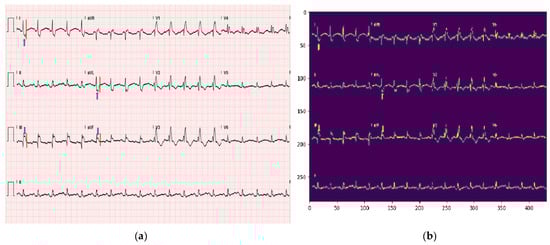

3.2.1. Dataset

- Load the “ECG Images dataset of Cardiac Patients”, consisting of 12-lead-based ECG images and four classes (normal, myocardial infarction, previous history of MI, abnormal heartbeat).